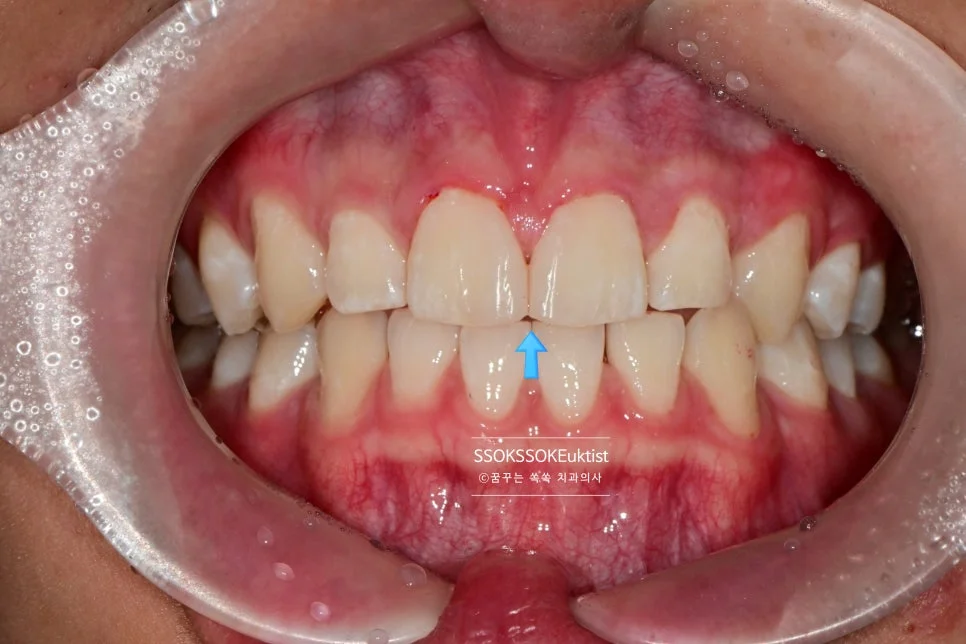

레진 치료는 어떻게 하면 될까요? 그저 예쁘게 치료하면 됩니다^^ 복잡한 치료 내용들은 굳이 아실 필요 없습니다^^

예쁘게 잘 치료된 것 같으신가요? 그럼 그냥 OK입니다!

그리고 안쪽에 닿는 점을 조정하여 치아가 벌어지는 경향을 최소화해주면 치료는 종결됩니다.

한 달 정도 후의 모습으로, 비교적 잘 유지되고 있는 것을 확인할 수 있습니다!